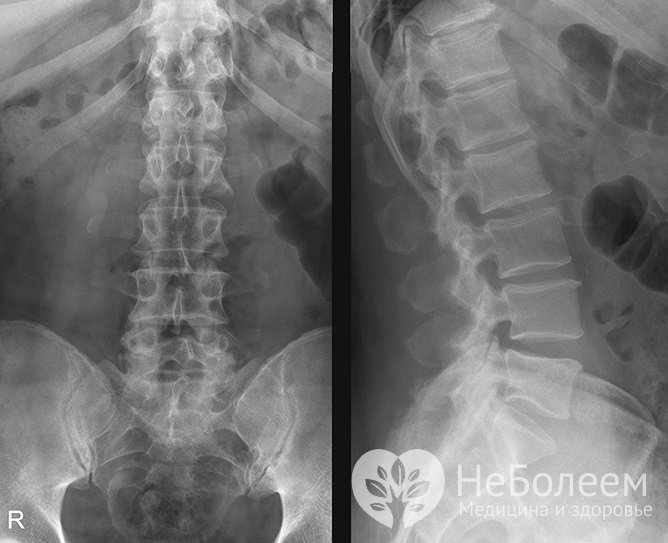

Для уточнения диагноза назначается рентгенСреди инструментальных исследований показана рентгенография одного или нескольких отделов позвоночного столба, которая позволяет выявить остеохондроз.

Для более детального изучения назначается компьютерная томография или магнитно-резонансная томография. Эти методы позволяют визуализировать состояние межпозвоночных дисков, определить остеофиты, косвенно указывающие на костно-хрящевую структуру исследуемой области.